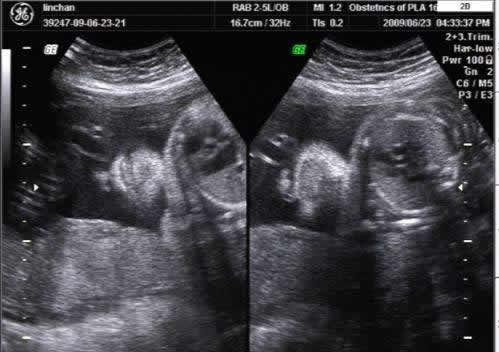

随着医疗技术的不断发展,孕妇在怀孕期间做产检是必备的过程。4维彩超的出现更是成为了不少孕妈妈产检的首要选择,那么问题来了,产检必须做4维彩超吗?4维彩超到底检查什么呢?这个问题据说80%的妈妈都不知道!

首先产检四维彩超不是必须做的,完全自愿。四维彩超可以拍到宝宝的大致轮廓,或许可以帮助你辨别宝宝的性别。而且可以保存下来,当成是孩子的第一份礼物。但成像的前提是宝宝必须是正面且面部无遮挡,这种几率基本上是百分之五十吧,有时候需要碰碰运气。

四维彩超不再是仅仅感觉宝宝的呼吸和运动,而是可以亲眼目睹他们的一举一动和乖巧的秀容。更为重要的是,四维彩超能够多方位、多角度地观察宫内胎儿的生长发育情况,为早期诊断胎儿先天性体表畸形和先天性心脏疾病提供准确的科学依据。